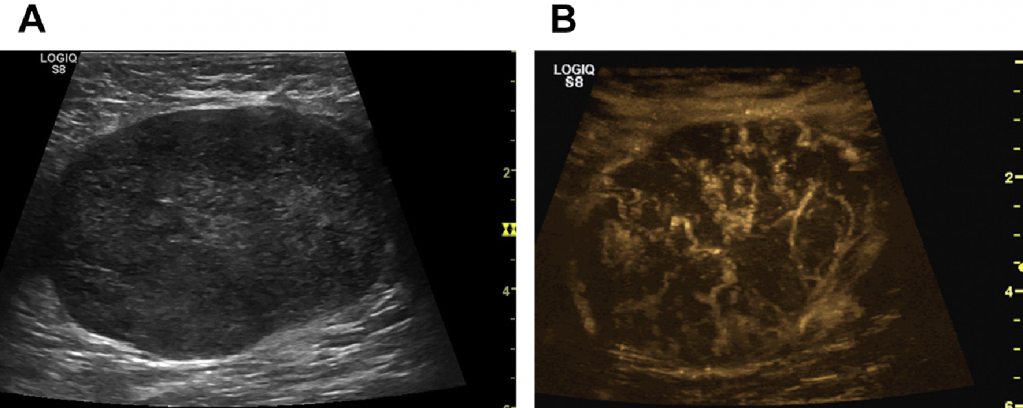

УЗИ лимфоузлов при лимфоме Ходжкина

Раздел: Образы вокруг